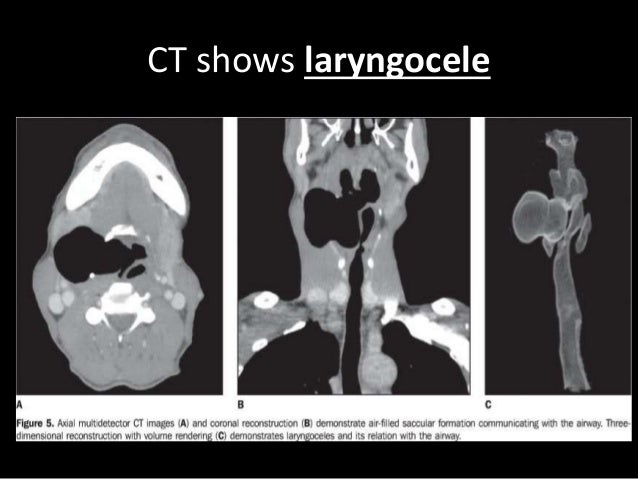

22. 22. Intrinsic • Part of Fibro-elastic Membrane which lies beneath the mucous membrane of the larynx. • The fibro-elastic membrane is divided into an upper and lower part by the laryngeal ventricle.

23. 23. Cricovocal membrane